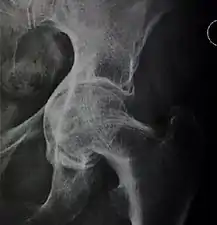

X-rays of hip dysplasia are one of the two main methods of medical imaging to diagnose hip dysplasia, the other one being medical ultrasonography.[1][2] Ultrasound imaging yields better results defining the anatomy until the cartilage is ossified. When the infant is around 3 months old a clear roentgenographic image can be achieved. Unfortunately the time the joint gives a good x-ray image is also the point at which nonsurgical treatment methods cease to give good results.

Adults

In the adult hip there are important landmarks to be recognized on plain film radiographs:[3]

- The iliopectineal or iliopubic line is formed by the arcuate line of the ilium and the superior border of the superior pubic ramus up to the pubic symphysis. It conforms to the inner margin of the pelvic ring and it is part of the anterior column of the acetabulum.

- The ilioischial line of Köhler begins at the medial border of the iliac wing and extends along the medial border of the ischium to end at the ischial tuberosity. It is part of the posterior column of the acetabulum.

- The acetabular floor.

- The teardrop represents a summation of shadows. Its medial aspect corresponds to the inner cortex of the pelvis and the lateral edge with the acetabular notch and the anteroinferior portion of the quadrilateral plate. It is not present at birth but gradually develops due to pressure of the femoral head.